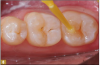

Giomer restoratives are bioactive regenerative materials that can be used where traditional direct composite materials are indicated. In the case presented in Figure 1, decay was noted on the occlusal surfaces of a first and second molar. What often looks like a very small amount of decay on the surface can lead to the discovery of significant dentin destruction. The quadrant was isolated and air abrasion was performed using 50 µm aluminum oxide (Figure 2). The occlusal groove enamel was abraded, revealing obvious decay to the dentin (Figure 3). Decay was identified with caries indicator and removed with a #2 round bur and slow-speed handpiece, with the goal of preserving as much healthy tooth structure as possible (Figure 4). Caries indicator stains denatured collagen and debris and helps to identify areas needing attention by the dentist, but equally importantly, it identifies areas without damage that can be preserved.

Fig 1. Subtle decay, occlusal view.

Figure 1